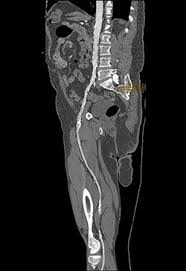

![]() L’angioscanner (scanner des artères) et l’IRM (Imagerie par Résonnance Magnétique) sont des examens peu invasifs sauf en cas d’insuffisance rénale associée. |

![]() L’artériographie est souvent très utile avec une injection directe de produit de contraste intra artèrielle. |